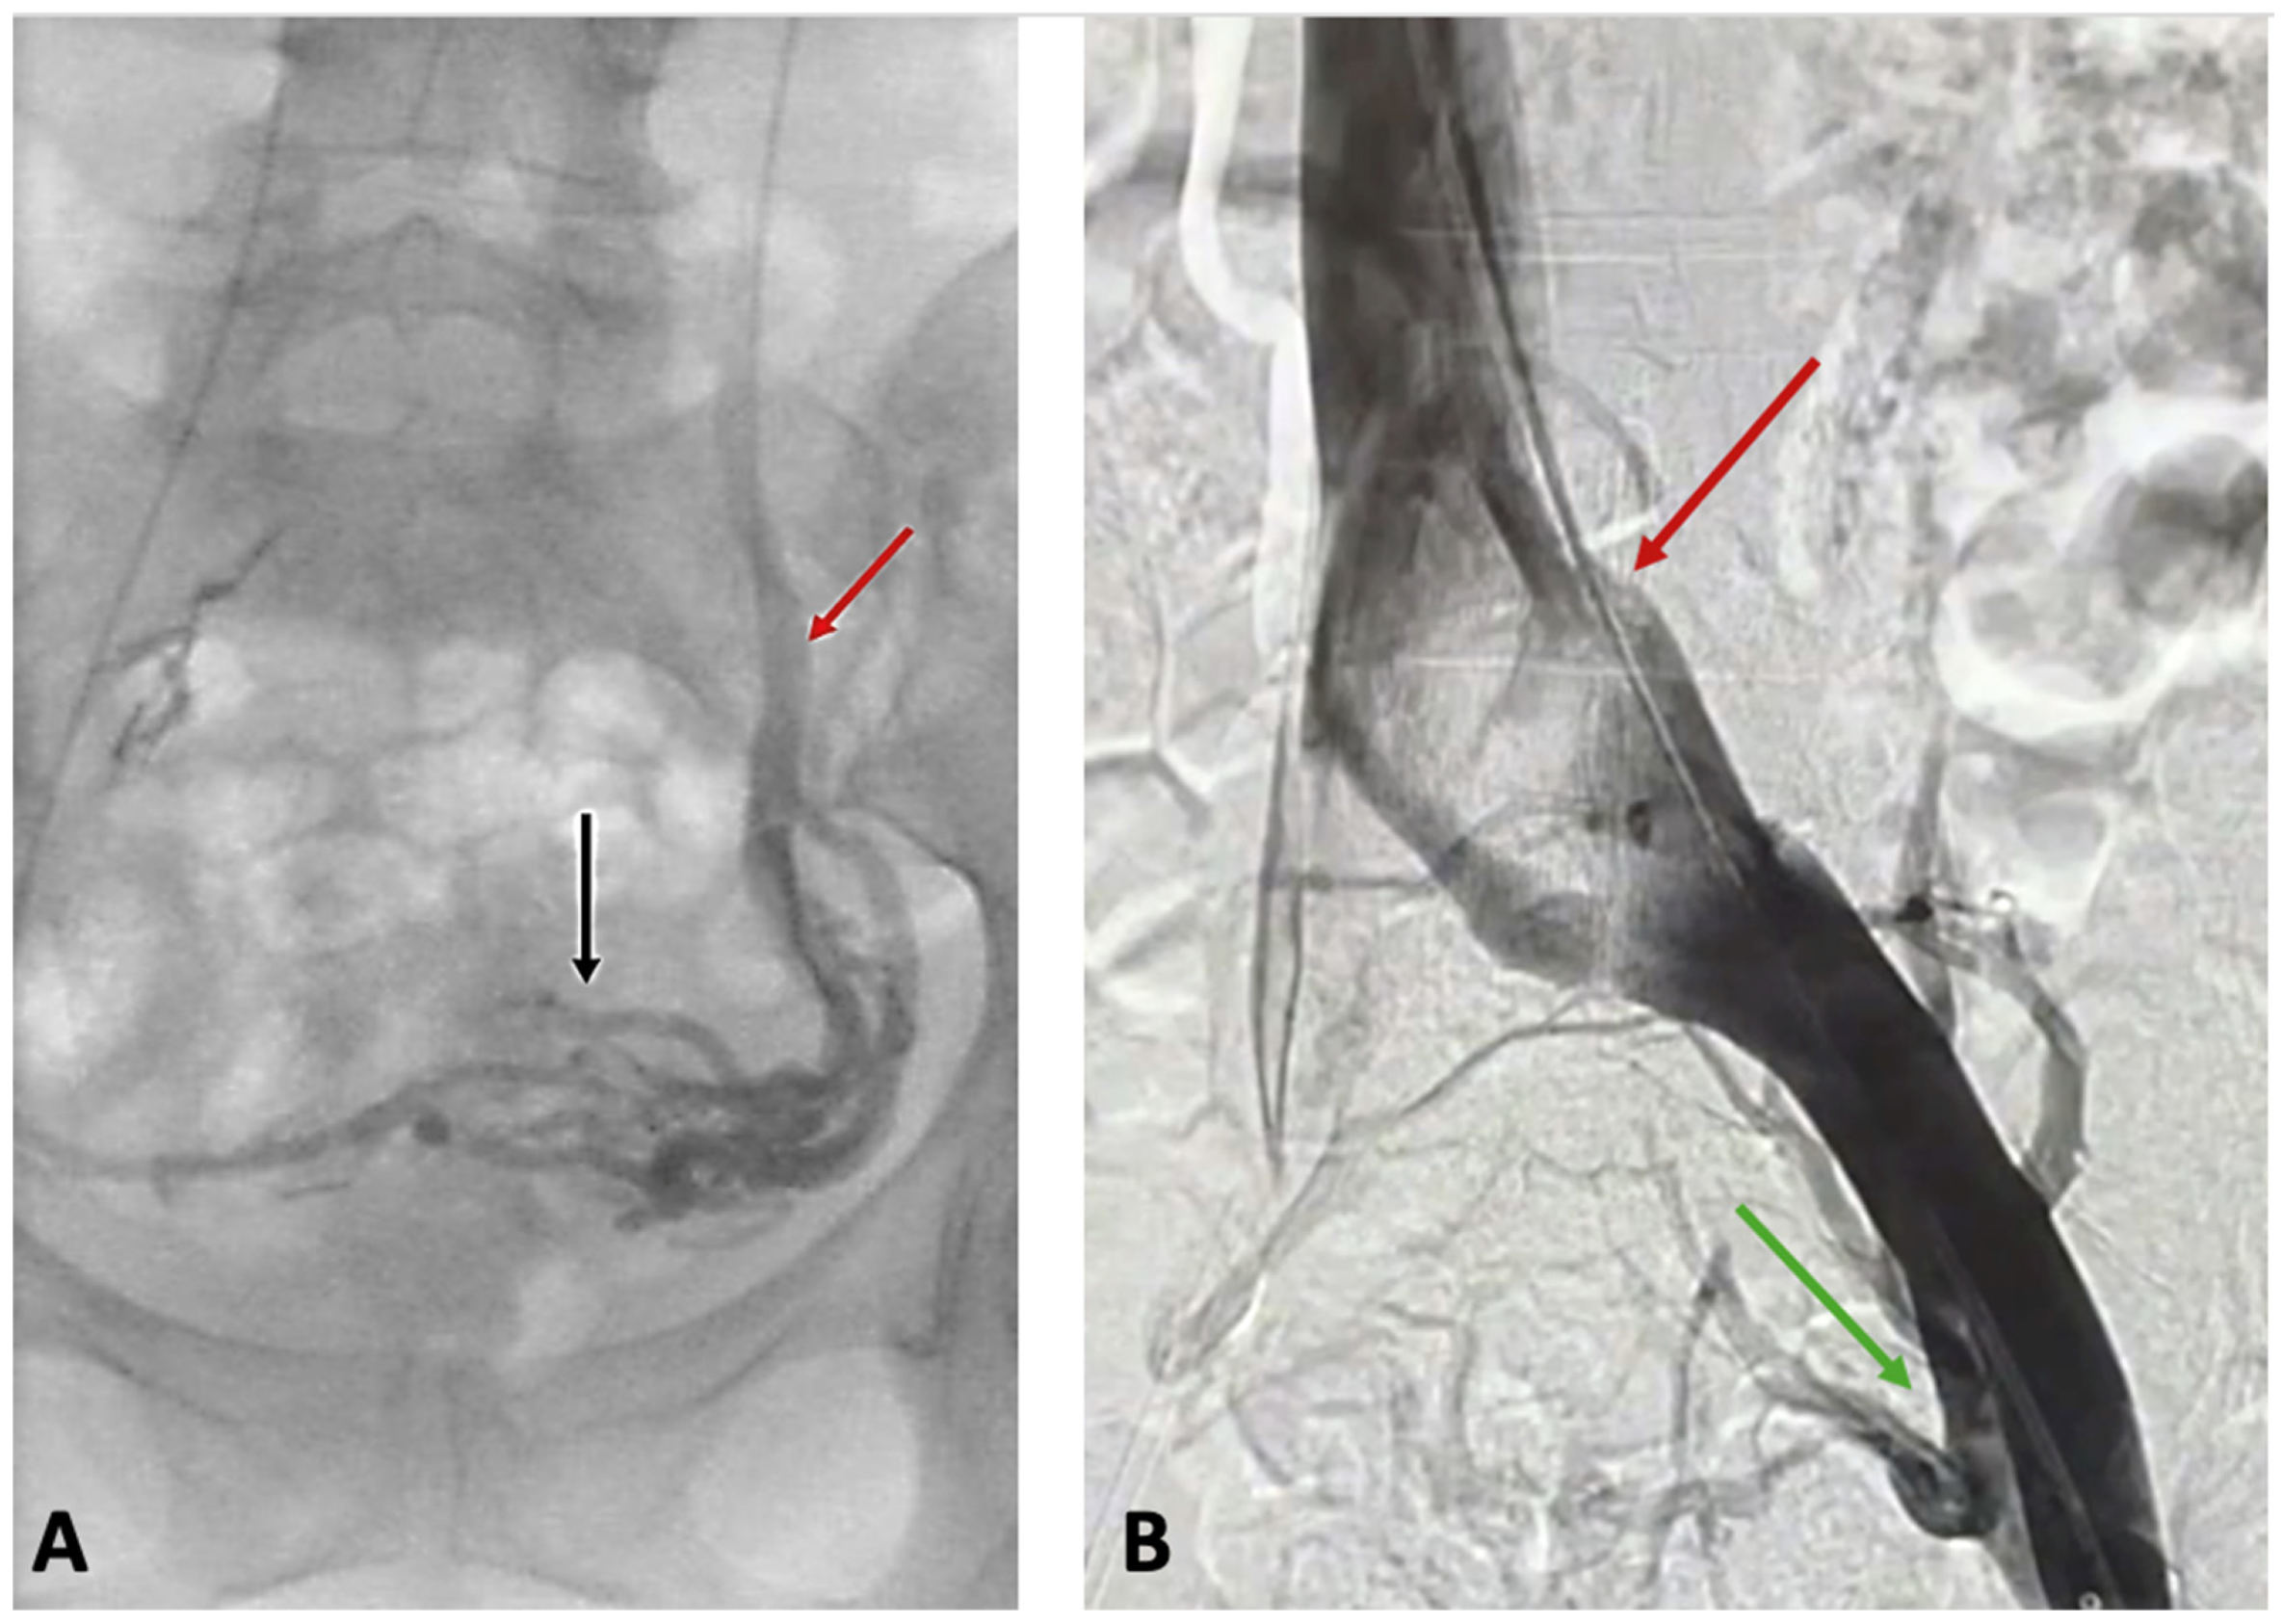

2.3.2. Catheter Venography and Intravascular Ultrasound